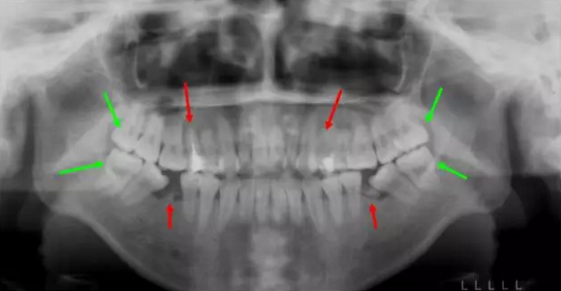

13.png

這個妹子正畸前,前牙不能咬合,牙凸又嘴凸而且還有殘余的牙根,牙列開始傾斜。綜合考慮后,醫(yī)生拔除了箭頭所示8顆牙,沒有采取常規(guī)拔牙,因為需要盡量拔除不能保留的病牙。